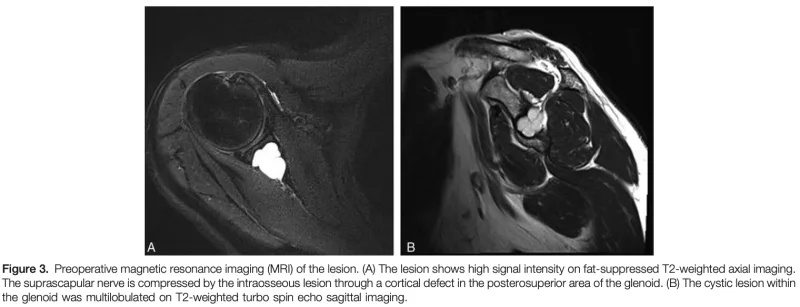

肩甲骨関節窩部にT2強調画像で液体の貯留を示す白く写る病変が認められます.

先輩医師の整形外科クリニックから, 肩甲骨関節窩の骨破壊を指摘され, 骨腫瘍が疑われる中高年の患者さんが紹介されました.

MRIでは液体貯留を示唆する所見があり, 骨内ガングリオンが疑われましたが, 軟骨性腫瘍を否定するため, 造影MRIを撮像し直すことにしました.

病変は周辺部のみが造影され, 内部には造影効果を認めず, 嚢腫性病変と判断.

骨内ガングリオンの診断が確定しました.

肩関節痛はありましたが, 腱板断裂と肩関節拘縮によるもので, 骨内ガングリオンとは関連がないと判断.